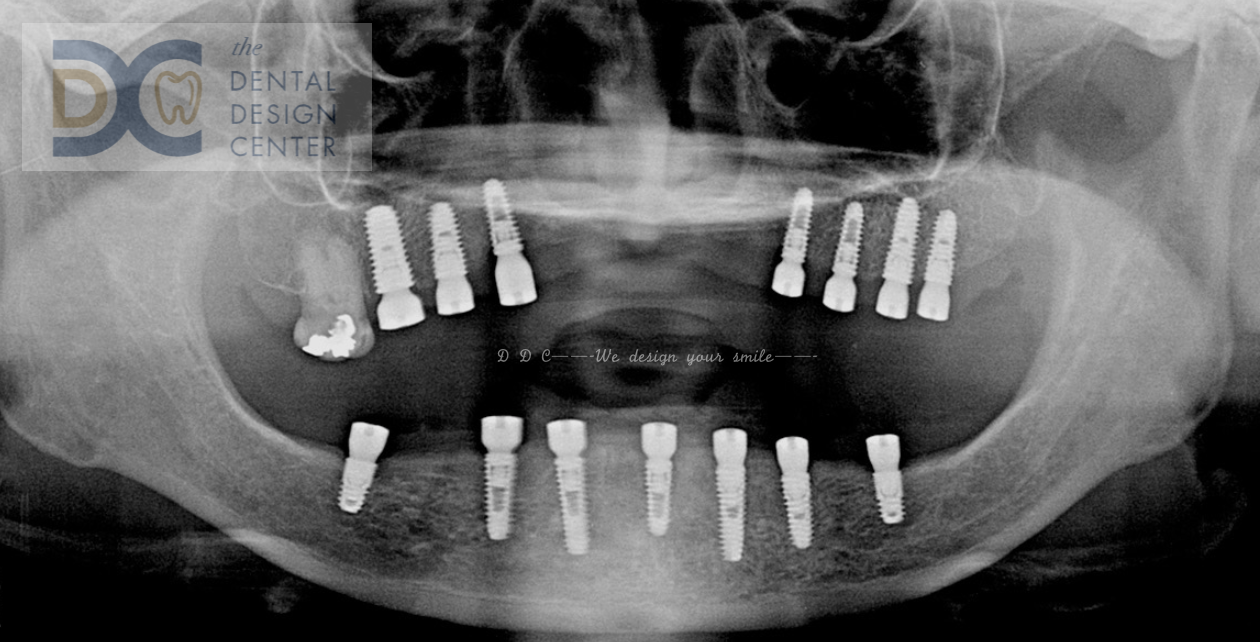

Full mouth implants in severe maxillary resorbed ridge.

Initial OPG x-ray and intra-oral picture show a failed mandibular natural teeth bridge.

Due to the severely resorbed ridge, implants were placed in the posterior maxilla.